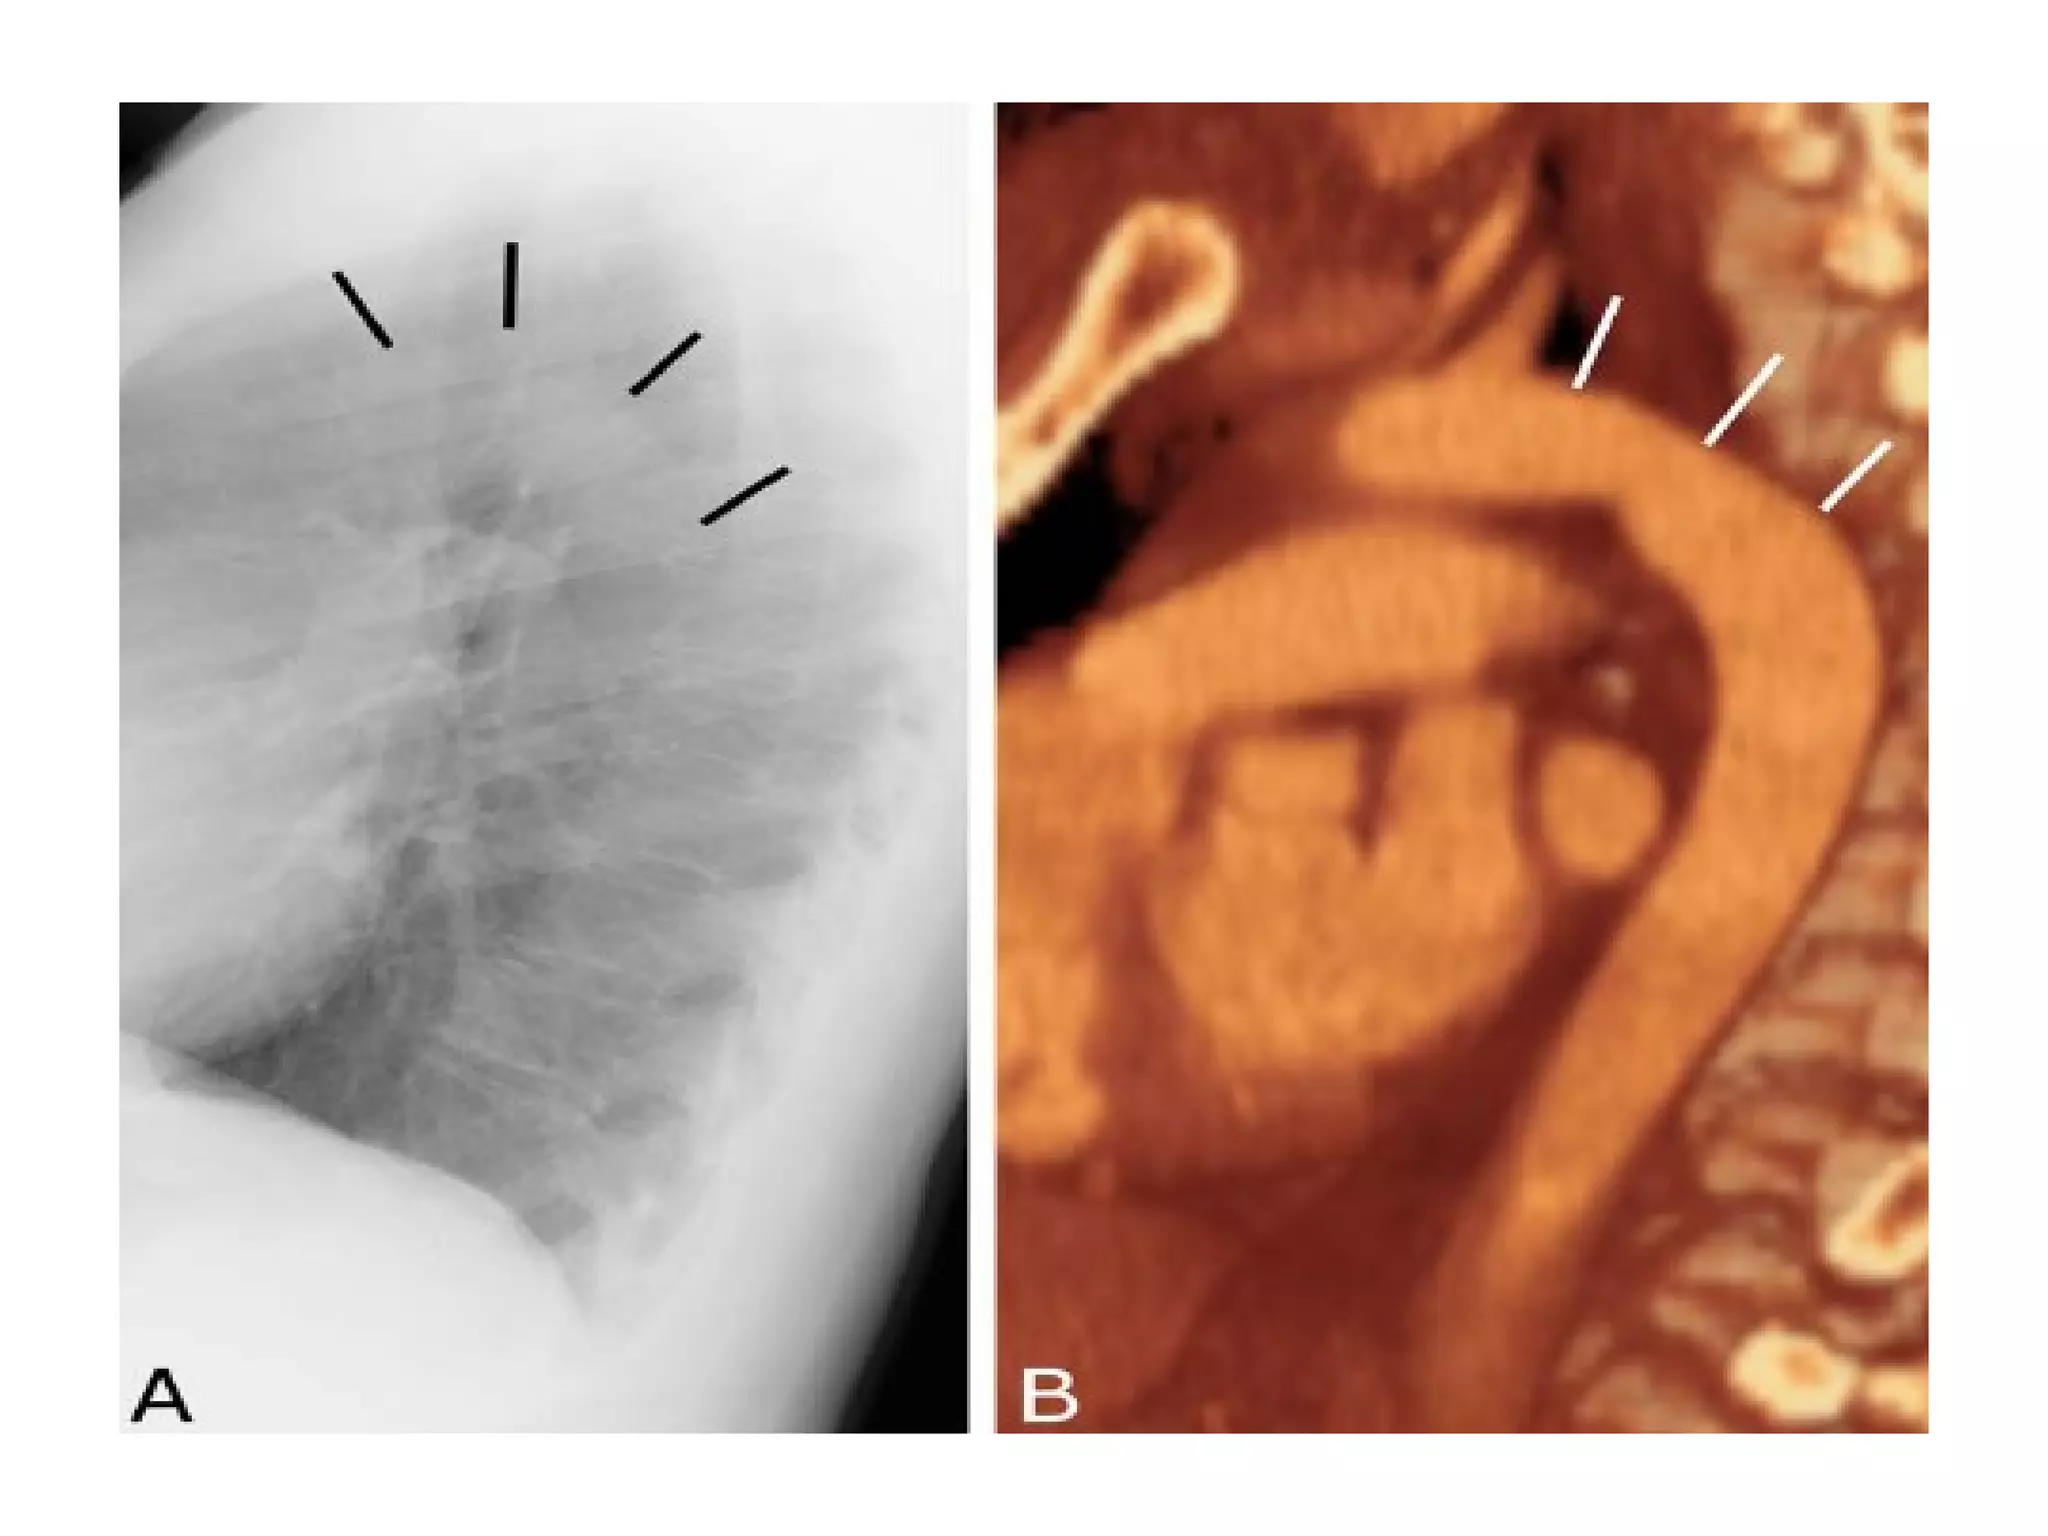

The fissures

The main fissures

The horizontal fissure is seen often incompletely

on PA film

The oblique fissures are seen on lateral film

commence posteriorly at the level of T4 or T5

passing through the hilum. The left is steeper

and finishes 5cm behind the anterior

costophrenic angle, where as the right ends just

behind the angle.

Viewing the lateral film

• Routinely the left side is adjacent to the

film

lateral

• Aortic arch

• Right pulmonary

artery

• Left pulmonary

• Trachea & bronchi

• The clear spaces

Retrosternal space normally this space is less than 3 cm

deep

Retrocardiac space

• Vertebral translucency

The vertebral bodies become more

translucent caudally

The fissures The mainfissures The horizontal fissure is seen often incompletely on PA film The oblique fissures are seen on lateral film commence posteriorly at the level of T4 or T5 passing through the hilum. The left is steeper and finishes 5cm behind the anterior costophrenic angle, where as the right ends just behind the angle. Accessory fissures, the azygos fissure is comma shaped and nearly always right sided.